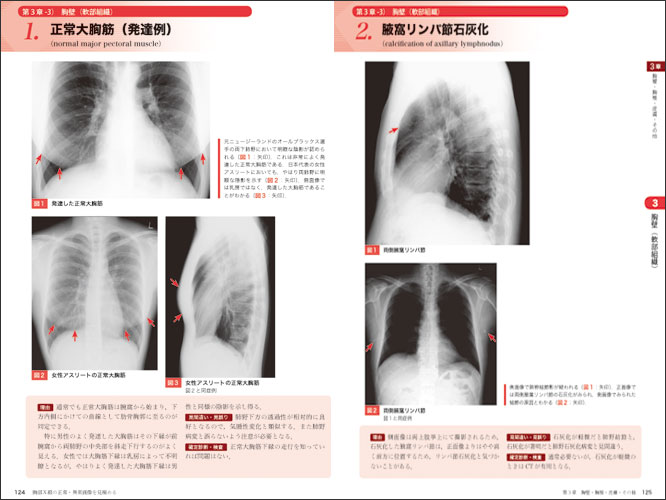

輝い 胸部X線画像診断アトラス 疾患が読める! | 江口研二 吉澤靖之, 医学一般